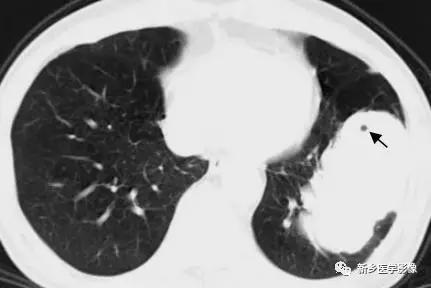

胸部CT肺窗圖;顯示空泡徵(↑)